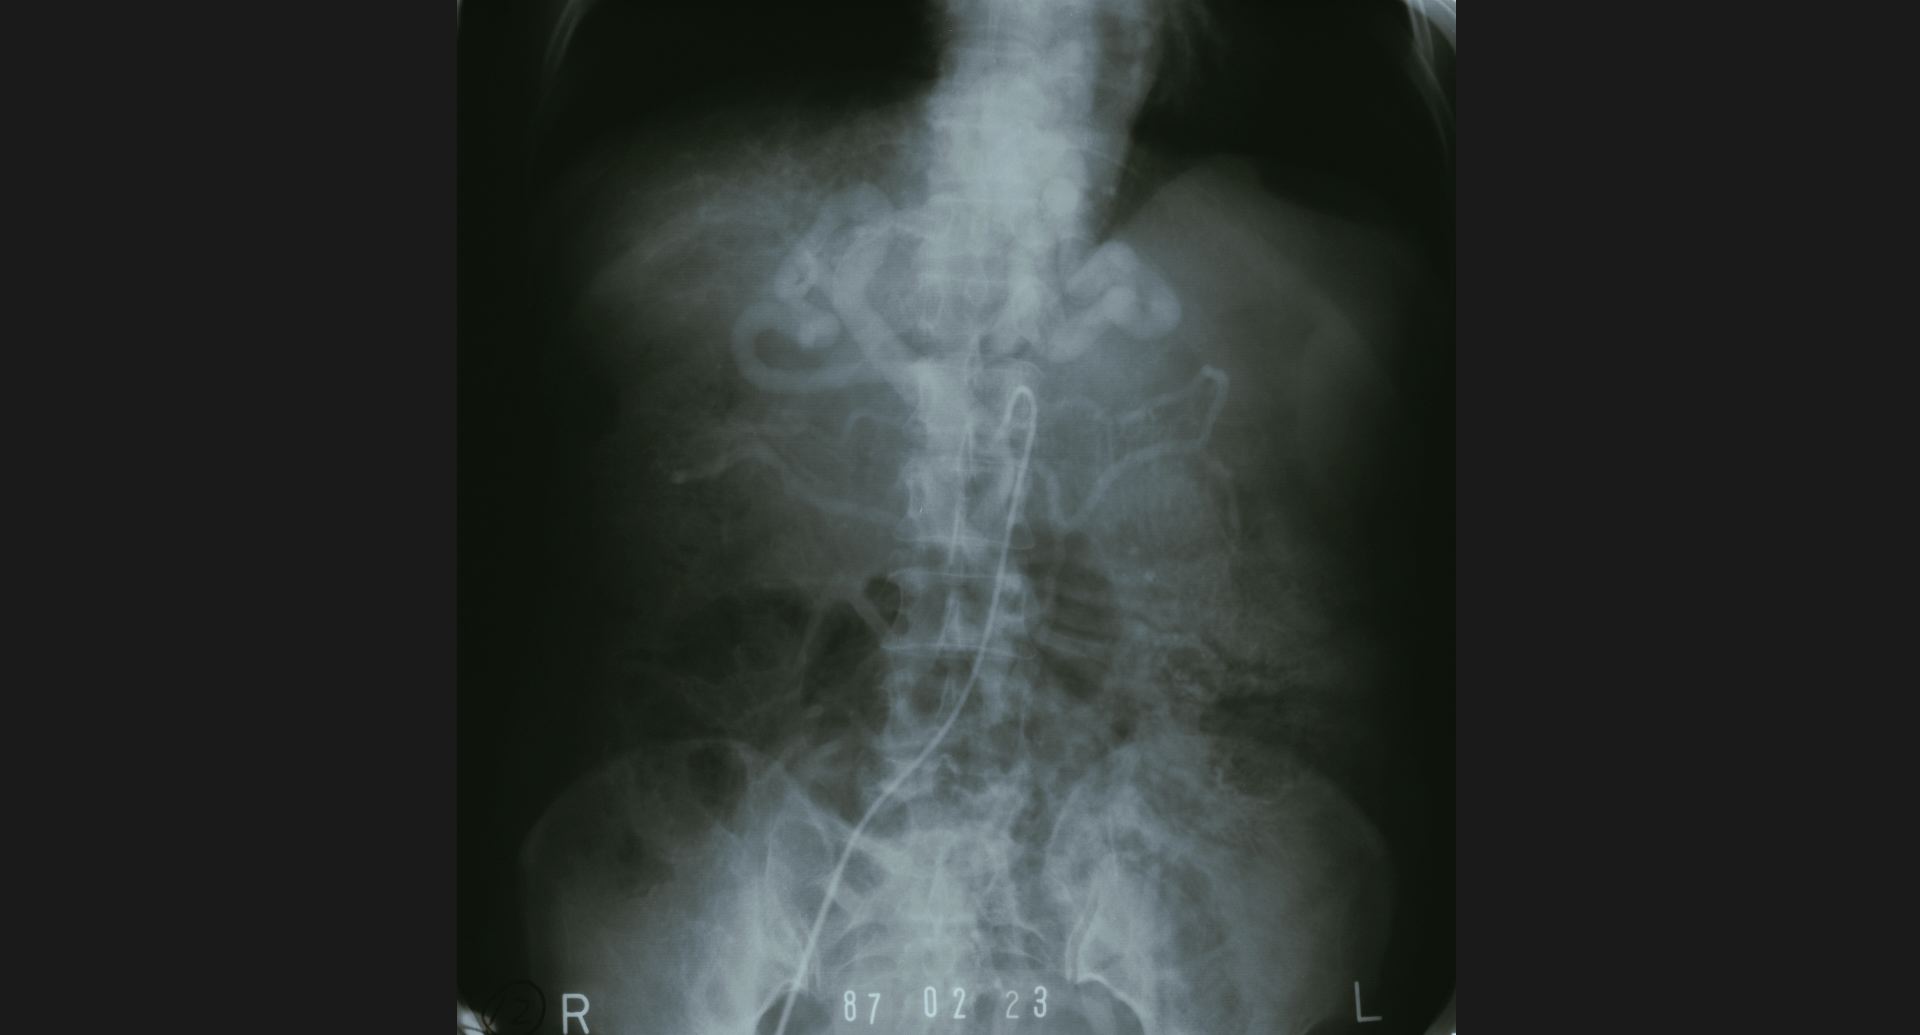

fig.3(105KB) :食道狭窄、肺炎

食道狭窄は、double aortic archによる。 肺炎は、造影の細かいところ。